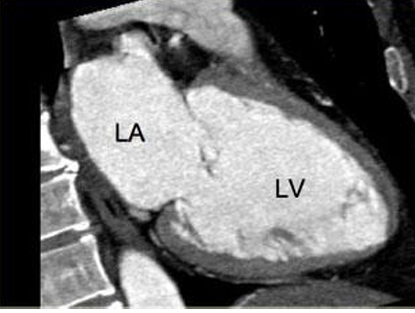

• LV: Left Ventricle

• RV: Right Ventricle

• LA: Left Atrium

• RA: Right Atrium

4 chamber view

Cardiac MRI- Cardiac Axes

3 chamber view

2 chamber view, 3 chamber view, 4 chamber view, 5 chamber view

Cardiac MRI- Cardiac Axes (4)